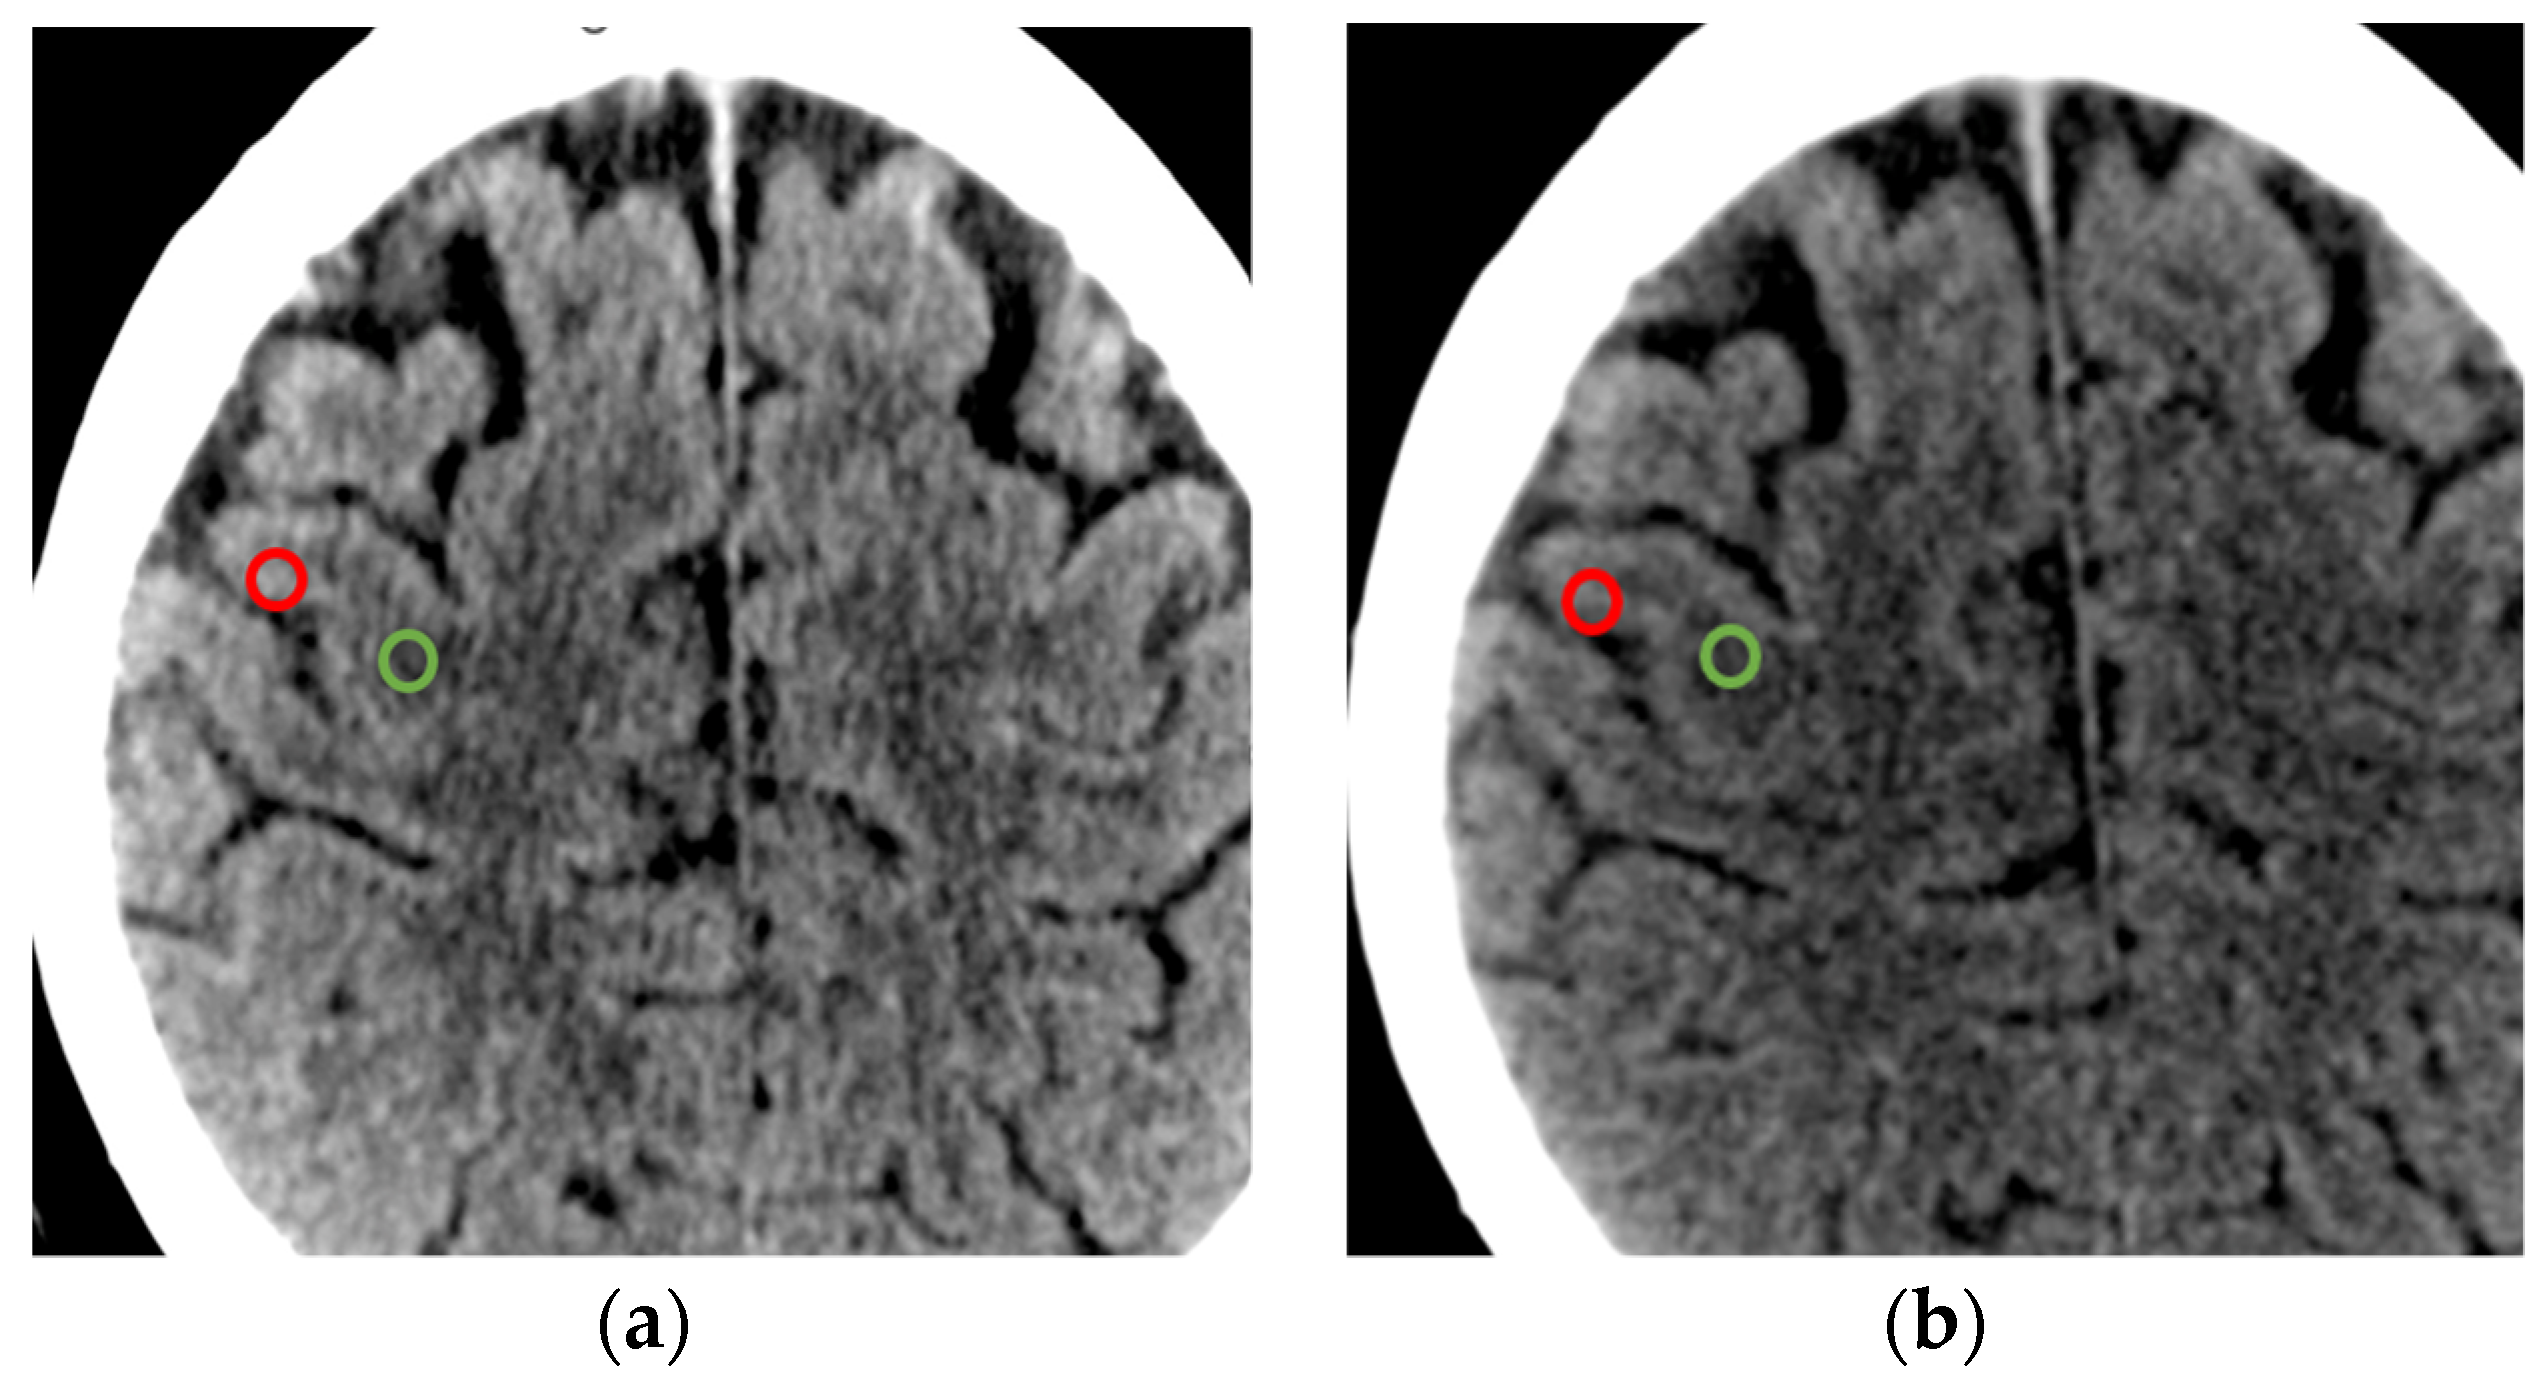

3.3. Imaging Specification: Comparison of the SNR (Signal-to-Noise Ratio)

3.4. Imaging Specification Comparison of the CNR (Contrast-to-Noise Ratio)